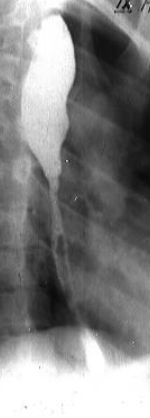

Neoplasm faringo-esofagian malign

Neoplasm esofagian malign